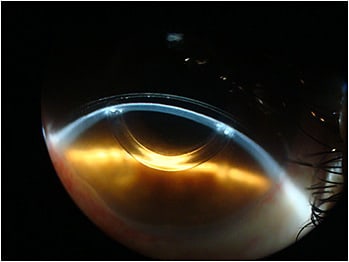

Both lenses had similar parameters of base curve 45.00D (7.50mm), power -5.00D, overall diameter (OAD) 16.5mm, and 0.27mm central thickness. During slit-lamp examination, we found that the lenses were too tight, both compressing the sclera and causing blanching and impingement (Figure 2).

We also observed that the scleral lens vault was excessive, due to an overestimated sagittal height (sag) value.

A higher vault may be tolerated in some cases, especially when you fit the larger, full scleral lenses that have diameters of 18mm and greater. But an excessive vault may also result in corneal hypoxia and subsequent corneal edema. Figure 3 shows the lens vault at presentation.